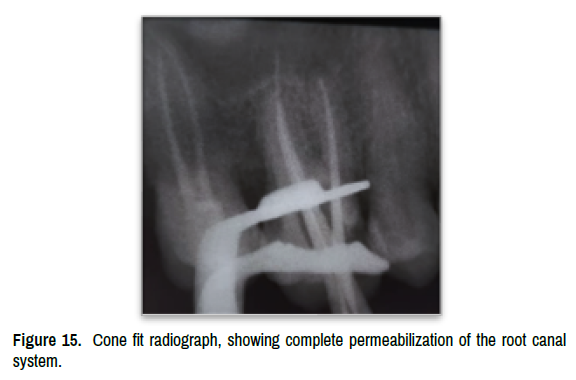

Using the same long-necked ball bur, the calcified tissue was abraded under direct visual control, using the color difference (between cameral dentin and calcified tissue) as a milling guide. This was continued until complete removal of the pulpolite and release of the canal orifices. Once free, root canal negotiation and instrumentation were carried out step by step, with continuous renewal of the irrigation solution (Figures 13-15).

Figure 15. Cone fit radiograph, showing complete permeabilization of the root canal system.